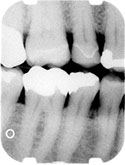

Before/After Photos